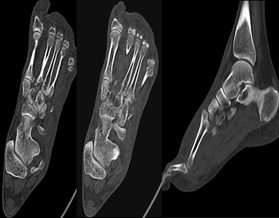

2.相较于X线检查,CT和MRI检查可提供更多信息:

• CT可以显示平片阴性的轻微骨折或半脱位,可以沿关节长轴或短轴进行重建;